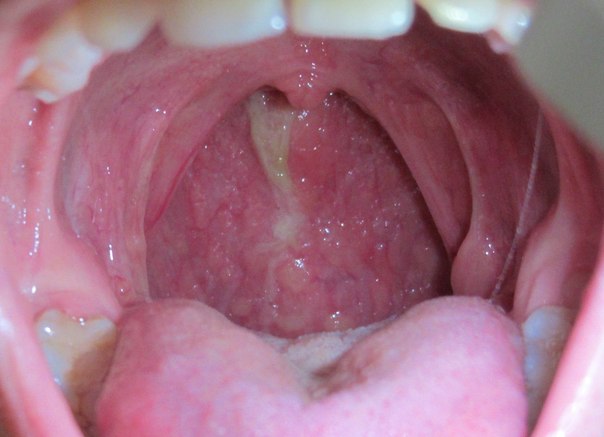

Рак Миндалины Отзывы Форум